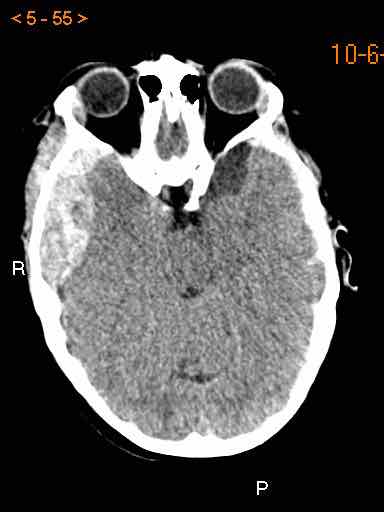

Các hình ảnh cho thấy máu tăng tỷ trọng trong khoang dưới nhện của rãnh Sylvius (mũi tên vàng).

Lưu ý xuất huyết dưới da đầu vùng chẩm phải (mũi tên xanh).

Đây là dạng tổn thương chấn thương kiểu coup-contrecoup.